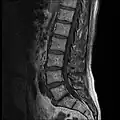

The lumbar vertebrae are located between the thoracic vertebrae and pelvis. They form the lower part of the back in humans, and the tail end of the back in quadrupeds. In humans, there are five lumbar vertebrae. The term is used to describe the anatomy of humans and quadrupeds, such as horses, pigs, or cattle. These bones are found in particular cuts of meat, including tenderloin or sirloin steak.

In human anatomy, the five vertebrae are between the rib cage and the pelvis. They are the largest segments of the vertebral column and are characterized by the absence of the foramen transversarium within the transverse process (since it is only found in the cervical region) and by the absence of facets on the sides of the body (as found only in the thoracic region). They are designated L1 to L5, starting at the top. The lumbar vertebrae help support the weight of the body, and permit movement.